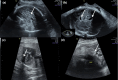

Methods: We used whole-exome sequencing in a consanguineous Turkish family with four siblings presenting with Pierre Robin sequence, arthrogryposis, heart malformation, splenomegaly, hydrocephaly, corpus callosum dysgenesis, brainstem, and cerebellar hypoplasia.

Results: We identified a novel homozygous pathogenic variant in exon 9 of COG6 (NM_020751.2): c.821del, p.(Arg274Lysfs*32). In this family, our post-mortem study led us to describe further the prenatal phenotype of CDG2L. In addition, it permits correlating the most relevant anomalies to a maldevelopmental cascade due to a neurodegenerative process of metabolic origin, affecting the entire central nervous system including the spinal cord.